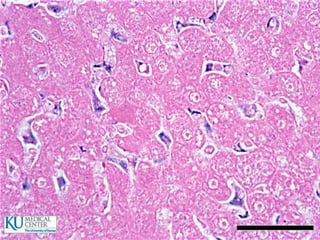

Glándulas salivales principales

 Glándula parótida

 Glándula submaxila

 Glándula sublingual